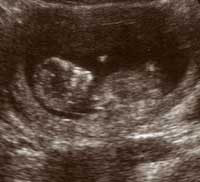

But what variability. 11-65%! Statistics hey? And pregnancy seems to be full of them. I met someone in India who during her pregnancy was given a test and told that she had a 300 to 1 chance of her baby having Downs Syndrome. This filled her with fear. But think of it as odds; would you back a 300 to 1 horse? In the litigious society we live in, hospitals are obliged to dazzle with facts and figures so the ambulance chasers can't have recourse later to say they weren't told. No doubt when we would have that scan we'll be full of the same fear.

Because this was only the first hurdle. Yet more statistics, the bane of the baby world, 20-30% of pregnancies end in miscarriage. Shit! How does that happen? The fear. Does Delhi belly bring it on? How do we minimise the risks? For once we could do something to mitigate against the fear. We could return home to the UK, where we could be confident of medical care and fine food and Vitamins for Pregnancy. And that is why circumstances drove us to the medical care back home. We would leave India early, our plans for India would remain unfulfilled. Instead, India would become our plan. The growing poppy-seed of life in Lindsey's womb took on the unknown sex of a girl and she was called India. (Well we could hardly call her Pushkar could we!)